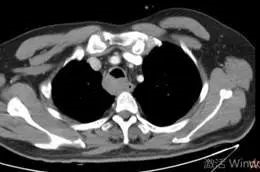

术后,患者第三天顺利拔除气管插管,胸闷、气喘等呼吸困难等症状完全缓解,复查胸部CT显示气管占位明显缩小,术后病理提示:气管囊性腺样癌。呼吸介入的成功治疗为患者进行下一步治疗提供宝贵的缓冲时间。

治疗后胸部CT